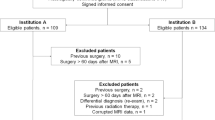

Two hundred and twenty-seven professionals working in 31 out of 51 European countries completed the survey; seven were duplicates from the same institution, resulting in responses from 220 institutions. A proportion of questionnaires (8.2 %) included in the analysis were submitted by individuals currently working outside Europe. Figure 1 provides an overview of the responses by country.

Typical glioma standard MRI protocols lasted between 20–60 min. The proportion of institutions per country that use protocols shorter than 30 min is displayed in Fig. 2.